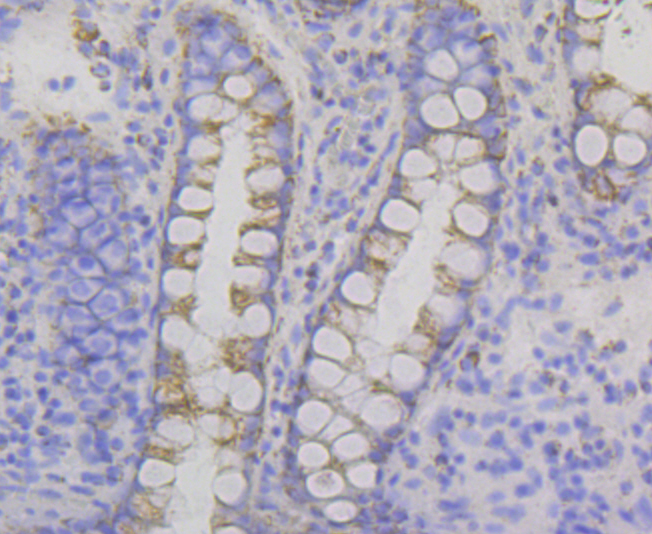

Immunohistochemical analysis of paraffin-embedded human colon tissue using anti-P2Y6 antibody. Counter stained with hematoxylin.